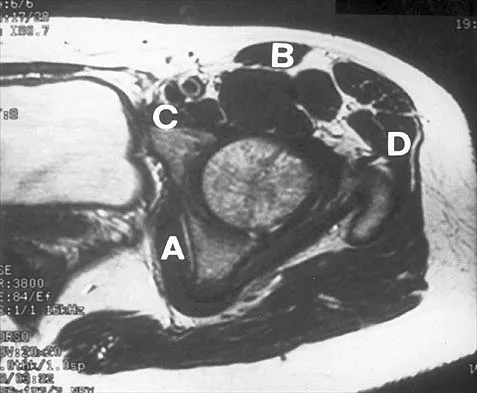

Figure 37 shows the T2-weighted MRI scan of the hip joint. What structure is labeled A?

Explanation